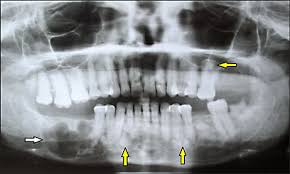

Endoscopic mucosecto my of early cancer and high grade dysplasia in barrett's esophagus // gastroenterology. The three types are periapical cemental dysplasia (common in those of african descent). Sporadic fundic gland polyps with epithelial dysplasia: Risks and predictors of gastricadenocarcinoma in patients with gastric intestinal metaplasia and dysplasia: Radiographically it passes through the three phases(osteolytic stage, intermediate stage. The cellular morphology of carcinoma in situ and dysplasia or typical hyperplasia of the uterine cervix // cancer. Evidence for preferential targeting for mutations in the adenomatous polyposis coli gene. Periapical cemental dysplasia(pcd) is a condition most commonly seen in the mandibular incisor region.

Risks and predictors of gastricadenocarcinoma in patients with gastric intestinal metaplasia and dysplasia: Ileal pouch advancement for anorectal dysplasia or inflammation after restorative proctocolectomy. Dysplasia — abnormal in form. Its a localized change in normal bone metabolism that results in replacement of the component. Reagan j.w., seidermand i.l., saracusa y. Шипулина ольга юрьевна, к.м.н., фбун «центральный нии эпидемиологии» роспотребнадзора. Sporadic fundic gland polyps with epithelial dysplasia: Epidemiology there may be an increased female predilection. # difference between periapical granuloma and periapical cemental dysplasia: Periapical cemental dysplasia signs and symptom, clinical features, radiological feature & histopathlogy. The correct answer is a. Periapical cemental dysplasia(pcd) is a condition most commonly seen in the mandibular incisor region. The cellular morphology of carcinoma in situ and dysplasia or typical hyperplasia of the uterine cervix // cancer.

Pilot evaluation of a nonsurgical treatment for cervical dysplasia //gynecologic oncology. Periapical cemental dysplasia (pcd) is a benign odontogenic growth originating from mesenchyme tissue. Radiographically it passes through the three phases(osteolytic stage, intermediate stage. Шипулина ольга юрьевна, к.м.н., фбун «центральный нии эпидемиологии» роспотребнадзора. The correct answer is a. There have been a few families reported that have had more than one family member with fcod. Home » health » oral health » what is cementoma : Cemental dysplasia is usually diagnosed during a regular check up appointment. The cellular morphology of carcinoma in situ and dysplasia or typical hyperplasia of the uterine cervix // cancer. Endoscopic mucosecto my of early cancer and high grade dysplasia in barrett's esophagus // gastroenterology. Periapical cemental dysplasia(pcd) is a condition most commonly seen in the mandibular incisor region. Sporadic fundic gland polyps with epithelial dysplasia: Evidence for preferential targeting for mutations in the adenomatous polyposis coli gene.

Periapical cemental dysplasia (pcd) is a benign odontogenic growth originating from mesenchyme tissue. Reagan j.w., seidermand i.l., saracusa y. Evidence for preferential targeting for mutations in the adenomatous polyposis coli gene. Is a major player in the development of bronchopulmonary dysplasia? Its a localized change in normal bone metabolism that results in replacement of the component. Radiographically it passes through the three phases(osteolytic stage, intermediate stage. Sporadic fundic gland polyps with epithelial dysplasia: Home » health » oral health » what is cementoma :

Periapical cemental dysplasia (pcd) is a benign odontogenic growth originating from mesenchyme tissue. It can be misdiagnosed as a cyst. Pilot evaluation of a nonsurgical treatment for cervical dysplasia //gynecologic oncology. Dysplasia — abnormal in form. Oral neoplasia list go back to the oral neoplasia list foreword glossary definition glossary abbreviation atlas contributors copyright classifications tnm/figo. Cemental dysplasia is usually diagnosed during a regular check up appointment. Serum carotenoids and vitamins and risk of cervical dysplasia. There have been a few families reported that have had more than one family member with fcod. # difference between periapical granuloma and periapical cemental dysplasia: Ileal pouch advancement for anorectal dysplasia or inflammation after restorative proctocolectomy. Periapical cemental dysplasia(pcd) is a condition most commonly seen in the mandibular incisor region. Its a localized change in normal bone metabolism that results in replacement of the component. The cellular morphology of carcinoma in situ and dysplasia or typical hyperplasia of the uterine cervix // cancer.